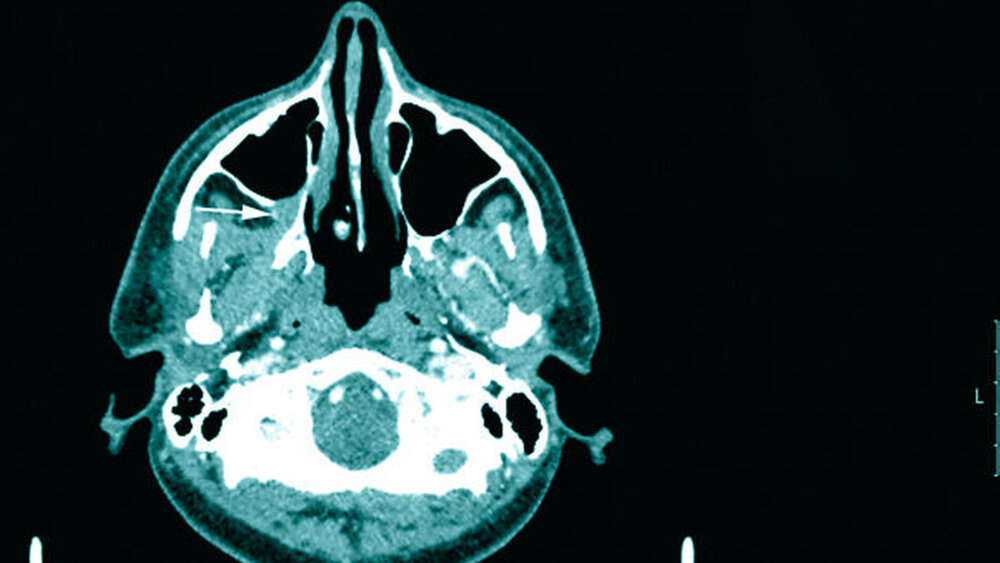

In der klinischen Untersuchung imponierte bei einem konservierend versorgten Gebiss eine reizlos verheilte Mundschleimhaut distal von 16 (Abbildung 2). Präoperativ wurde eine Computertomografie aus der Region gefahren, in der sich ein unscharf begrenzter Tumor im Bereich der distalen Maxilla und der Kieferhöhle zeigte (Abbildung 3).

Im Rahmen der Nachsorge wurde zwei Jahre später nach erneuter Anfertigung einer Computertomografie der Kopf-Hals-Region (Abbildung 6) der Verdacht auf ein Rezidiv gestellt, der sich durch eine Biopsie bestätigte. Nach erneuter Resektion des Befunds mittels navigierter Tumorentfernung über den alten Zugang und komplikationslosem Heilungsverlauf ist der Patient seit knapp zwei Jahren rezidivfrei.